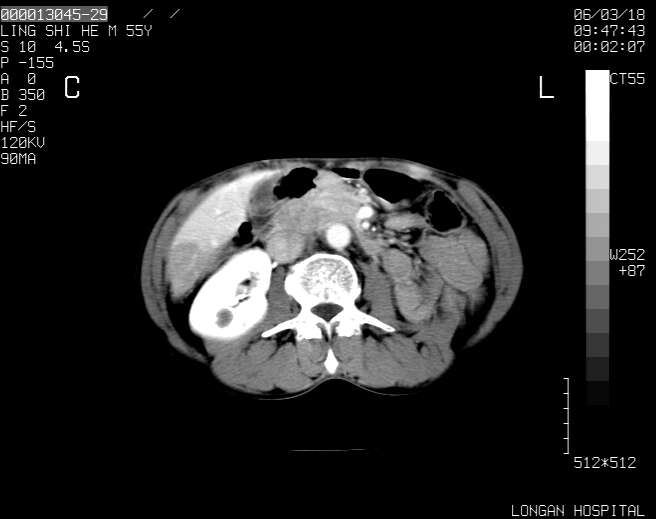

以下是引用guzhongliangddd在2006-3-21 22:13:00的发言:[br]病灶主要位于肝右叶的后份,内见异常血管,门脉主干及右支受侵{提示有癌栓形成},门腔间隙内见增大淋巴结。肝左叶内未见异常。

以下是引用zhuxinli在2006-3-22 1:23:00的发言:[br][br] 病灶主要位于肝右叶的后份,内见异常血管 .门脉右支截断,右叶前段早期强化(考虑动静脉漏),腹膜后肿大淋巴结,病灶逐渐强化,考虑为胆管细胞癌[br]